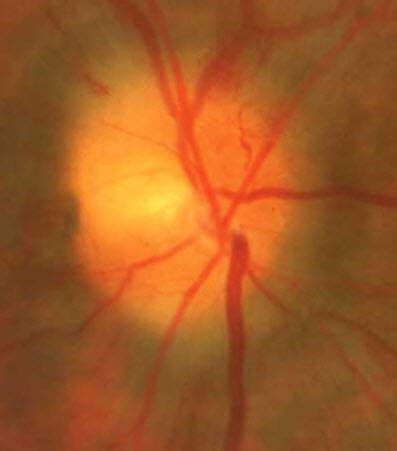

Ophthalmoscopic examination in patients who have NAION reveals optic disc edema that is sometimes diffuse but more typically shows sectoral involvement, with small flame-shaped hemorrhages and juxtapapillary arteriolar attenuation (Figure). A key diagnostic characteristic is a small, crowded optic disc with a small or nonexistent physiologic cup; this phenomenon is called the "disc at risk."5,6 In patients who present with acute disc edema and vision loss in one eye, the contralateral eye must be evaluated to determine whether there is a disc at risk. These patients are considered at elevated risk for NAION.